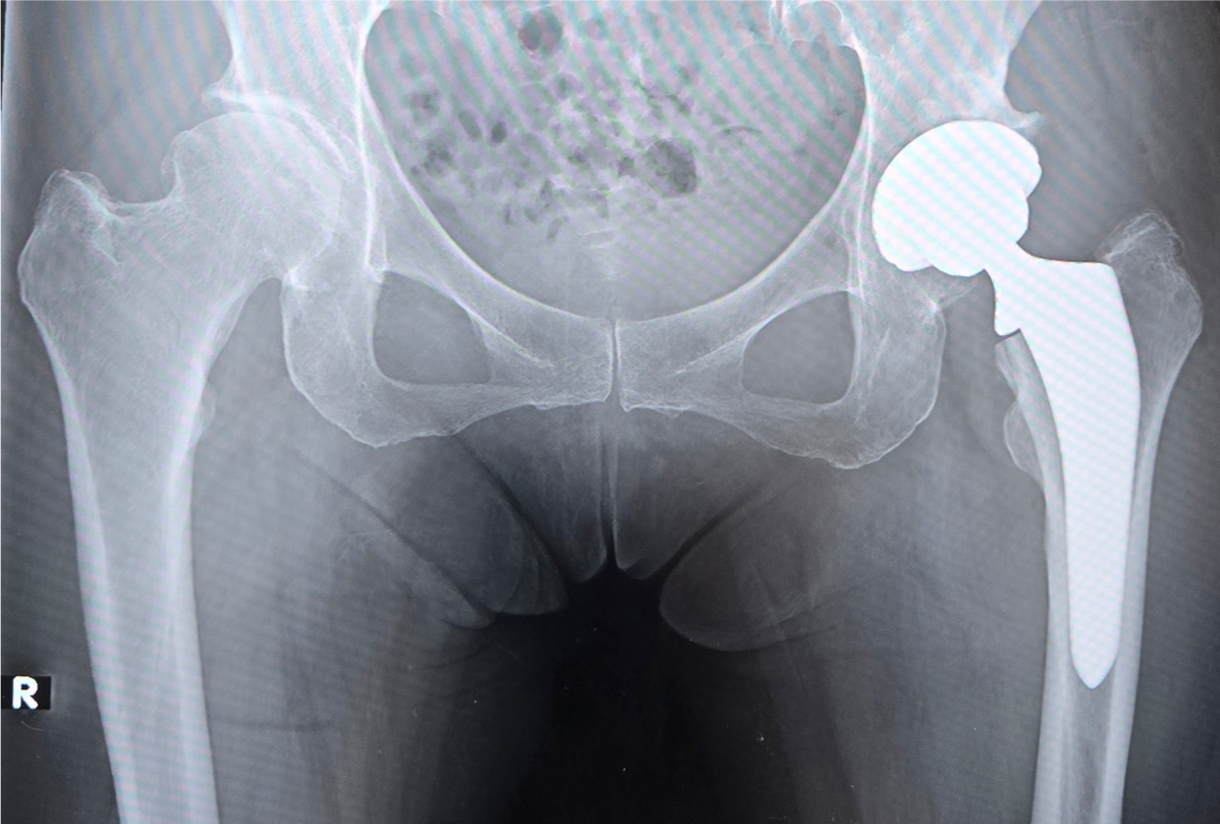

〈手術前のレントゲン〉

〈手術後のレントゲン〉(正面)

〈手術後のレントゲン〉(側面)

当院にて両側の人工股関節全置換術(THA)を施行。アプローチはAMIS(前方最小侵襲手術)で行い、術中に神経ブロックを併用することで、術後の疼痛コントロールを行い、術翌日から離床、リハビリを進めることができました。術後すぐに歩けることに本人も驚いていました。また、術後は一切の肢位の制限も行っていません。